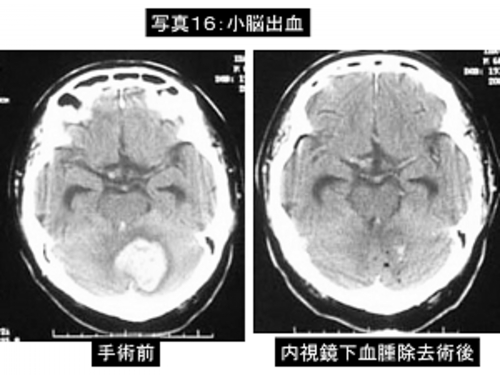

高齢者や全身合併症がある一部の脳内出血に関しては内視鏡による血腫除去術を行うことがあります。

手術時間は1時間から2時間で、患者さんへの侵襲が少ない手術ですが、出血の量が多くて脳のむくみがひどい場合は開頭術の方が有効です。

写真16:小脳出血に対する内視鏡下血腫除去術。左は入院時のCT像、右は手術後のCT像です。血腫はほぼ全部除去されています。